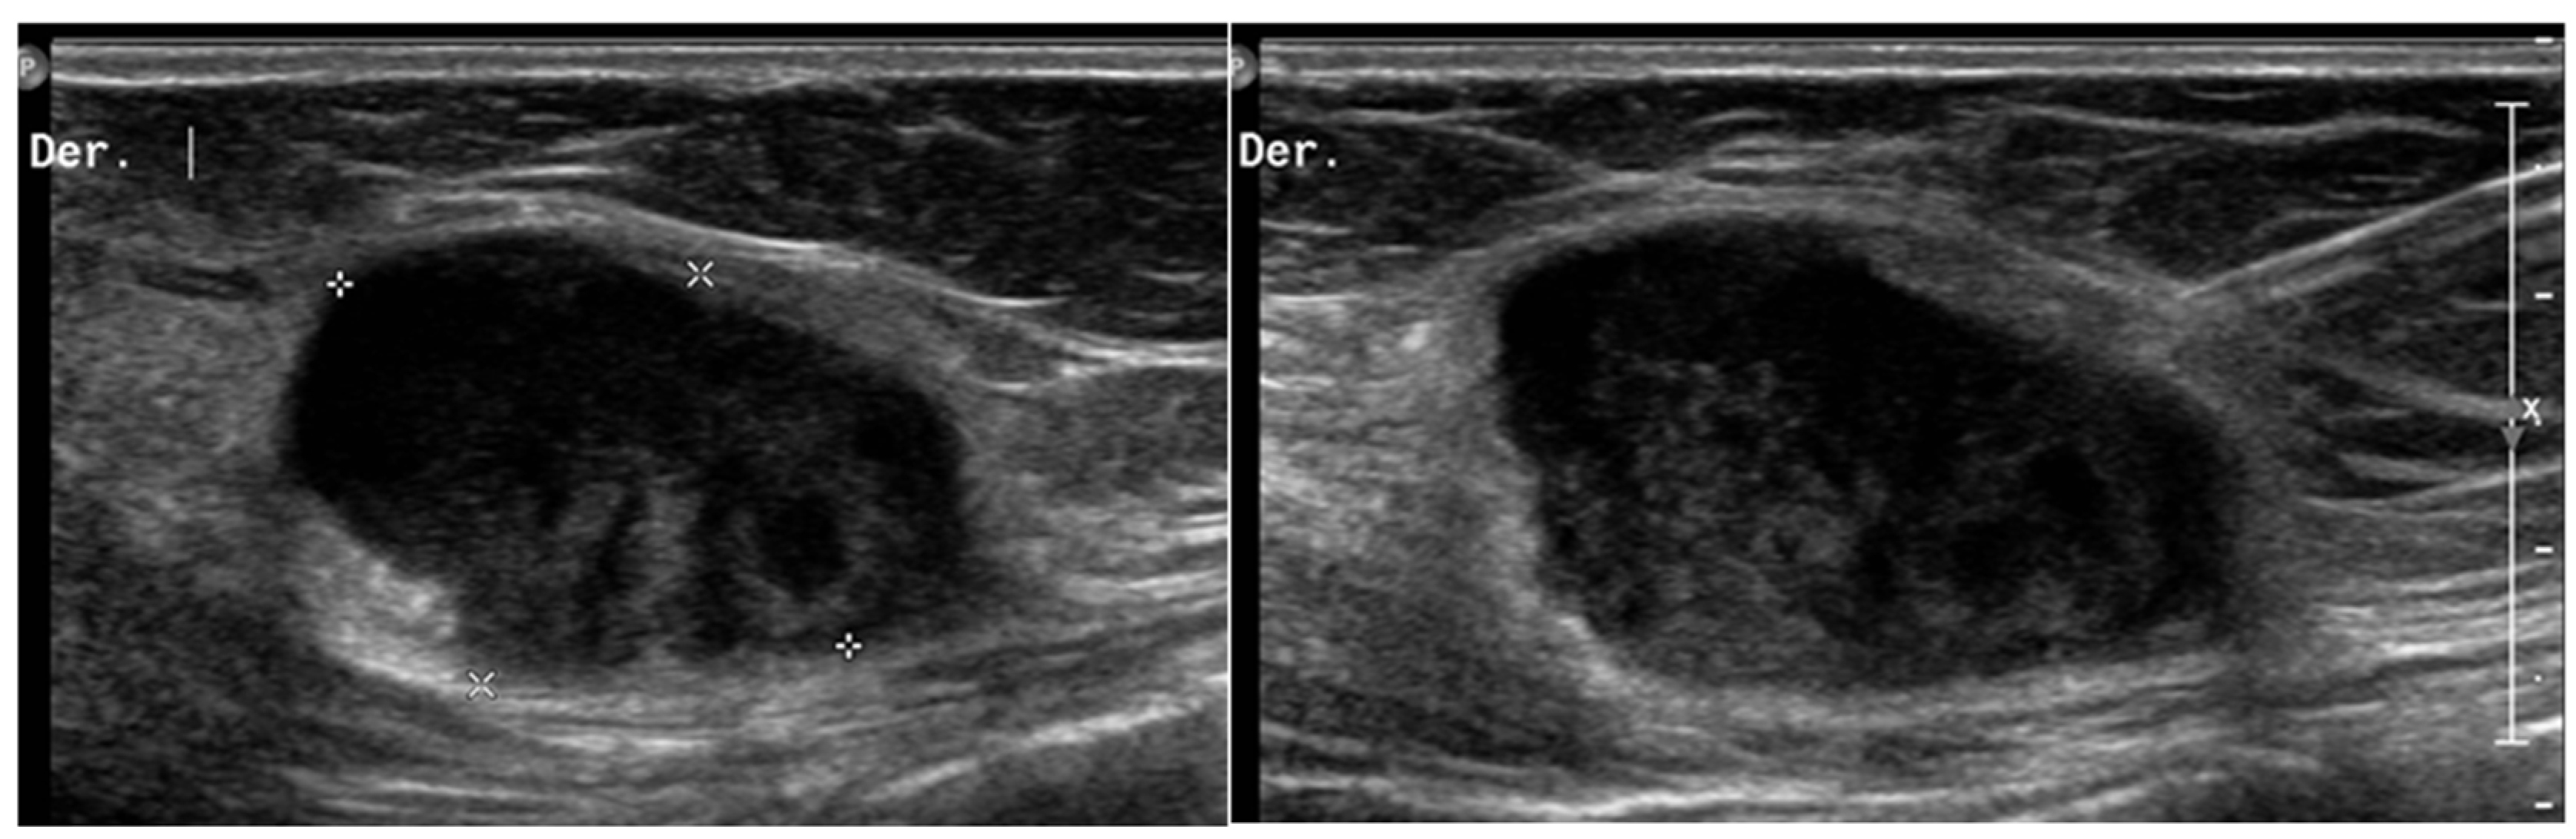

- Leiomyosarcomas: seen on the abdominal wall as either a primary process or as an extension of an intra-abdominal process [23,24]. Leiomyosarcomas demonstrate heterogeneous attenuation and signal intensity, with irregular peripheral enhancement and enhancing solid portions, mixed with hemorrhagic and necrotic areas [24]. Fatty components are absent (Figure 9) [23,24].

- Gastrointestinal Stromal Tumors (GIST): either primary (extraintestinal GIST, “EGIST”) [25,26] or secondary GIST of the abdominal wall are rare. When extended (>5 cm), GIST may have an aggressive behavior [25]. CT is the imaging modality of choice, showing heterogeneous vivid enhancement, and variable amount of necrosis. Peculiar findings include calcifications and cystic degeneration [27,28,29].